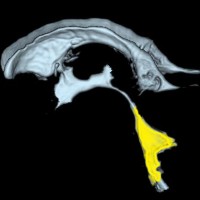

第4脳室とは

後頭部に近い所にあります。黄色が第4脳室で,髄液の通り道(出口)です。

前方には脳幹部,後ろは小脳虫部です 。

上は細い中脳水道につながって,下はマジャンディー孔と左右のルシュカ孔に開いています。